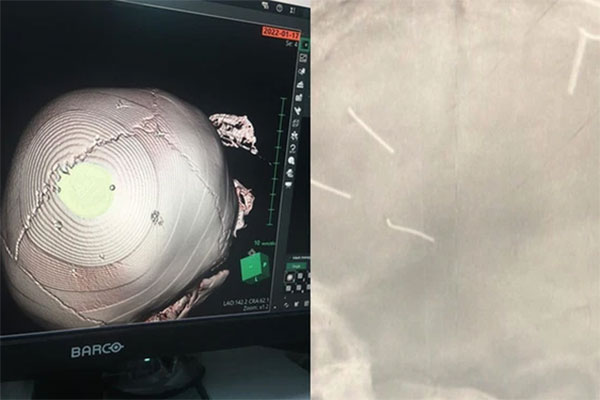

Hình ảnh chụp X-quang hộp sọ của bé A.